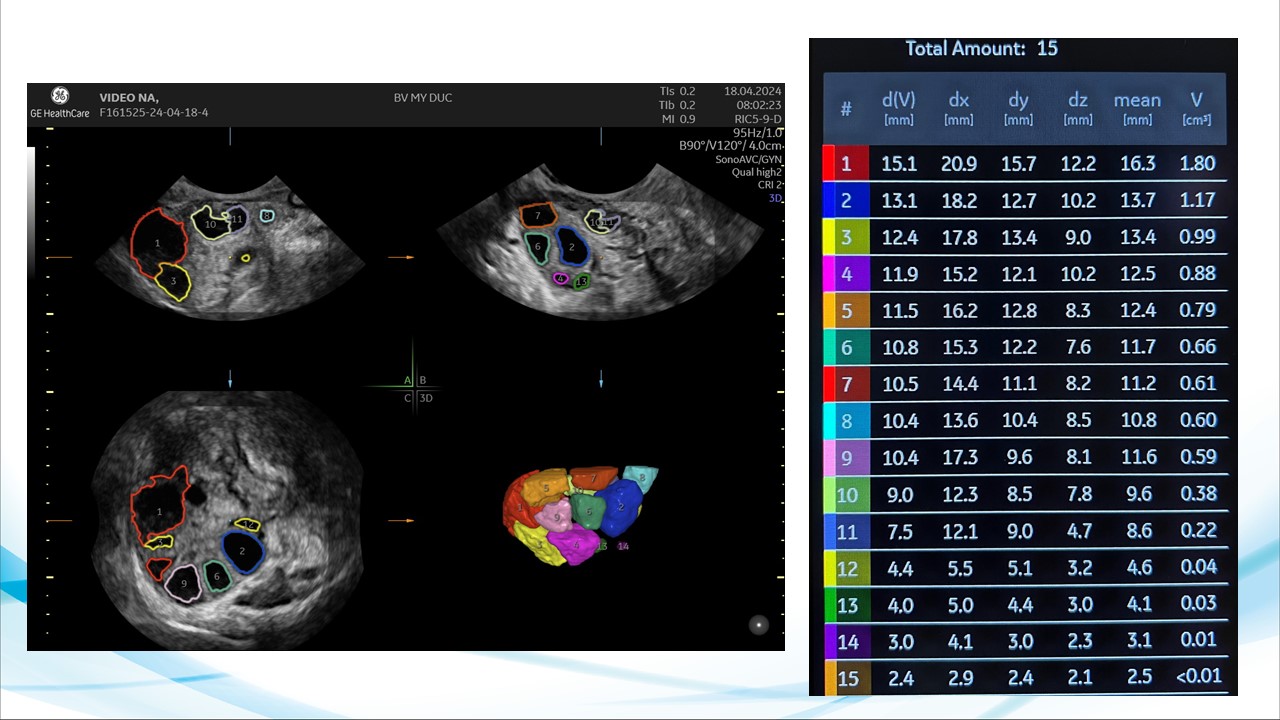

Siêu âm theo dõi trong bơm tinh trùng vào buồng tử cung và thụ tình trong ống nghiệm